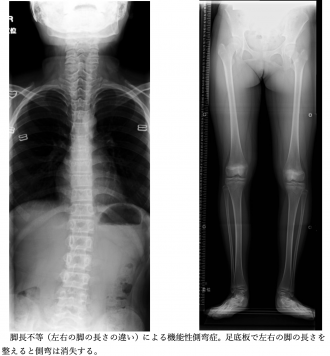

「1機能性側弯症」は、背骨の曲がり方の程度は軽く、原因を取り除くことによって側弯は消失します。

- 姿勢や左右の脚の⻑さの違い、腰痛などの原因で生じる「機能性側弯症」と、